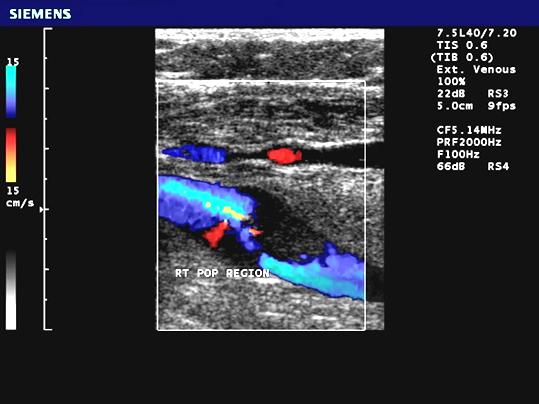

Subclavian steal

abnormal flow direction into the subclavian from the vertebral artery caused by stenosis of the subclavian

- Subclavian artery has a severe stenosis or occlusion

- Vertebral artery must compensate for the reduction of flow

- Becomes a collateral pathway to the extremity

- RETROGRADE flow or abnormal flow present in the vertebral arter

What side does subclavian steal syndrome usually occur?

left